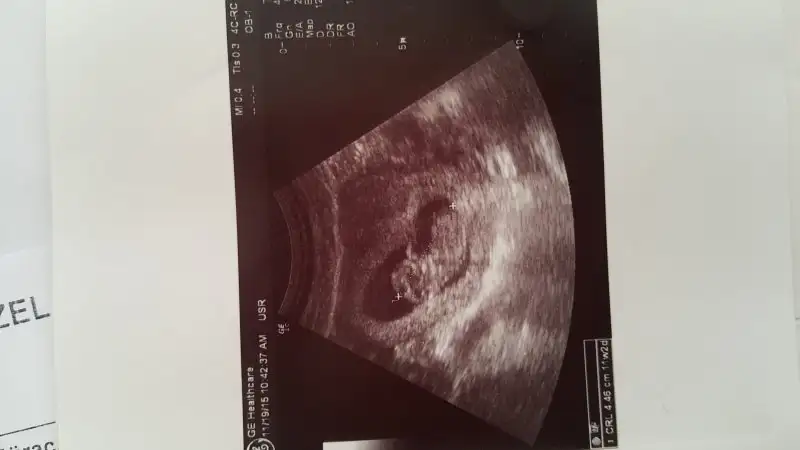

Merhaba arkadaşlar benimde ultrason resmimi yorumlarmısınız? Şimdiden çok teşekkürler:)

Eklentiler

• 20151128_081956.webp

20151128_081956.webp

11,7 KB · Görüntüleme: 89